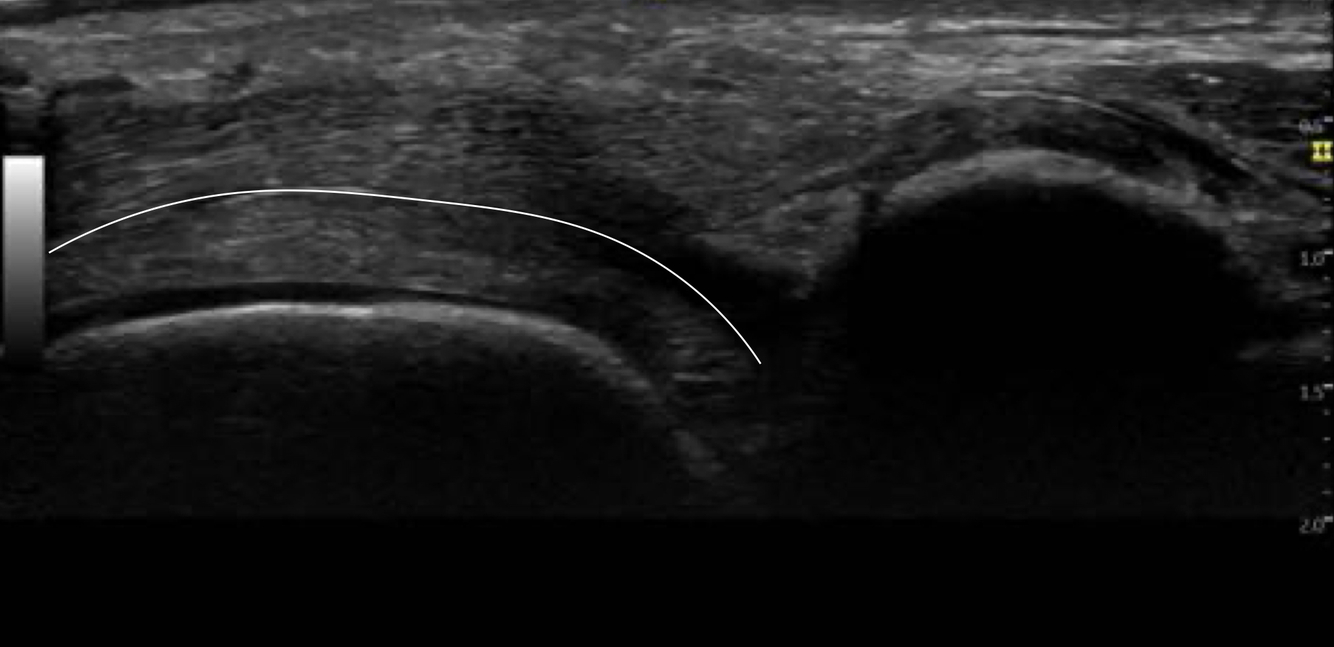

Identifier les structures sur cette image.

Indice: On y voit les os suivants : Tibia, talus et calcanéus

A